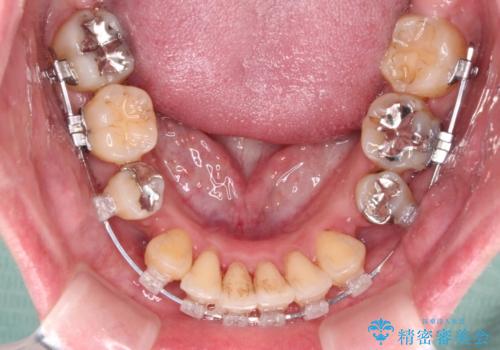

- クリアブラケット

- 2年9ヶ月

治療期間全体を通して歯の移動スピードがゆっくりであったので、当初予定よりも1年ほど長い、3年間を要することとなりました。